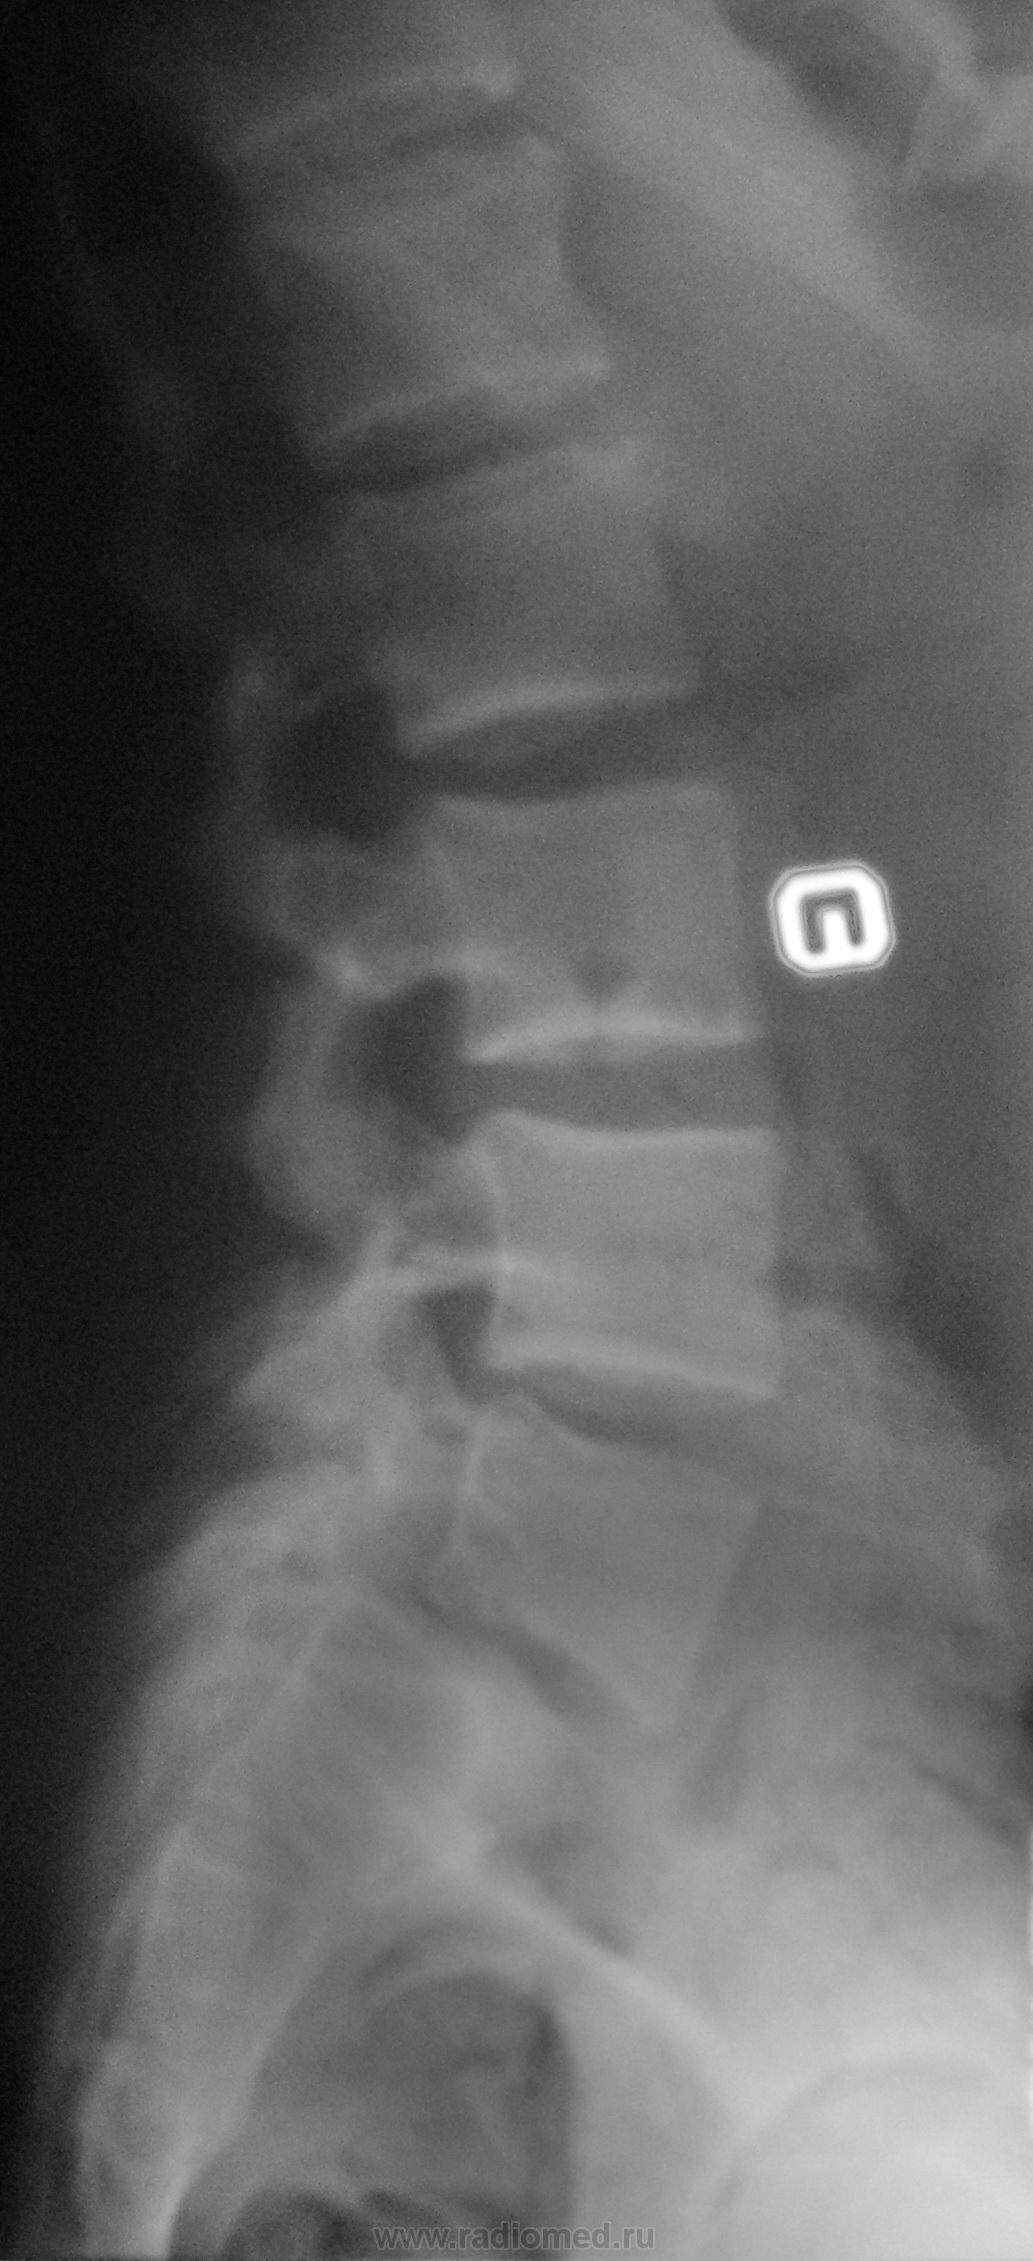

Молодой человек, занимаясь в спортзале, неаккуратно взял вес. Беспокоят боли в пояснице.

Истинный передний спондилолистез I степени и незаращение дужки L5

+1. Spina bifida S1.

На сколько я понимаю, при описании смещений в сегментах позвоночного столба принято оценивать смещение более краниального позвонка (как, например, при переломах оценивают смещение дистального отломка). С этой позиции, "Спондилолистез крестца кзади" звучит не совсем корректно.

На мой взгляд, сложно сказать явился ли листез следствием травмы (гипернагрузки), предыдущих снимков скорее всего нет. но исходя из умозаключения "где тонко, там и рвётся", смею предположить, что причина жалоб пациента находится именно на уровне спондилолистеза. ...правда, как облачить это в форму заключения протокола рентгенографического исследования я не знаю...

Если бы такой листез был следствием однократной гипернагрузки, думаю, что без инвалидной коляски бы не обошлось. Но о дальнейшем занятии таким спортом нужно задуматься.